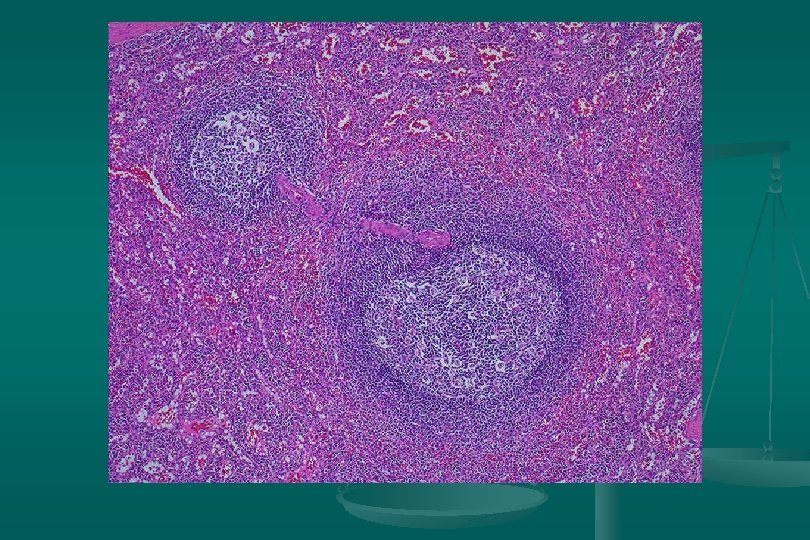

Enfermedad de Castleman Histología: dos categorías: 1. Tipo vascular hialino (angiofolicular): n Folículos grandes, proliferación vascular y hialinización central. n Capas concéntricas de linfocitos en la periferia del folículo (capas de cebolla). n Estroma interfolicular: prominente, venulas poscapilares hiperplásicas, CP, E. inmunoblastos n

Enfermedad de Castleman Subtipo linfoide: *Expansión zona del manto *Centros germinales pequeños. 2. Tipo células plasmáticas: n Proliferación difusa de cels plasm interfolicular + cuerpos de Russell n Cambio vascular-hialino: ausente n Depósito de material acidofílico amorfo (fibrina y complejos inmunes) n